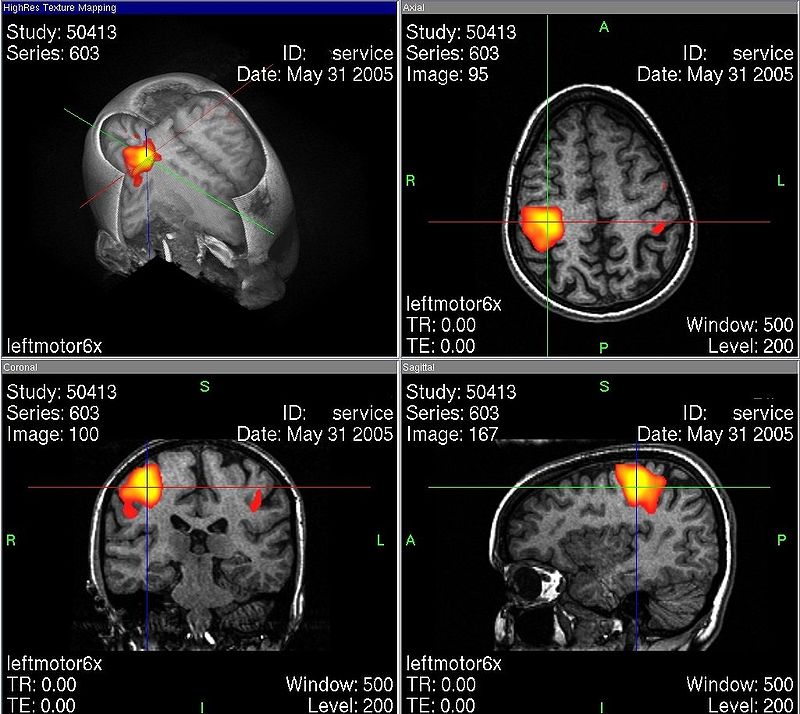

Toiminnallisella magneettikuvauksella (functional Magnetic Resonance Imaging, fMRI) voidaan tehokkaasti seurata erilaiten ärsykkeiden vaikutusta eri aivoalueilla. Tekniikka liittyy oletukseen, että veren happipitoisuudet aivojen eri osissa ovat kytköksissä aivojen aktivoitumiseen. Tutkimusmenetelmä on saanut myös kritiikkiä.

Veren virtaus aktiiviselle aivoalueelle muuttuu muutaman sekunnin kuluttua ärsykkeen havaitsemisesta ja aivoalueen sähköisestä aktivoitumisesta. Tietyn aivoalueen aivosolujen aktivoituminen vaatii energiaa. Lähde: Wikipedia: Toiminnallinen magneettikuvaus